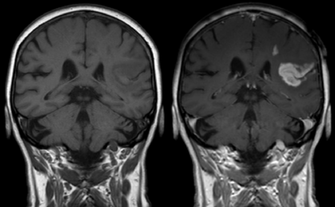

Gadolinium(III) containing MRI contrast agents (often termed simply "gado" or "gad") are the most commonly used for enhancement of vessels in MR angiography or for brain tumor enhancement associated with the degradation of the blood–brain barrier. For large vessels such as the aorta and its branches, the gadolinium(III) dose can be as low as 0.1 mmol per kg body mass. Higher concentrations are often used for finer vasculature.[3] Gd(III) chelates do not pass the intact blood–brain barrier because they are hydrophilic. Thus, these are useful in enhancing lesions and tumors where blood-brain barrier is compromised and the Gd(III) leaks out. In the rest of the body, the Gd(III) initially remains in the circulation but then distributes into the interstitial space or is eliminated by the kidneys.